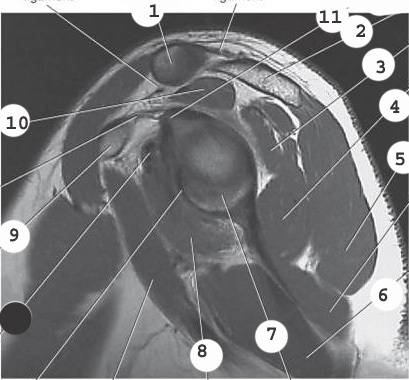

3

acromion

2

labrum

4

deltoid

5

glenoid

7

supraspinatis muscle

1

bicep